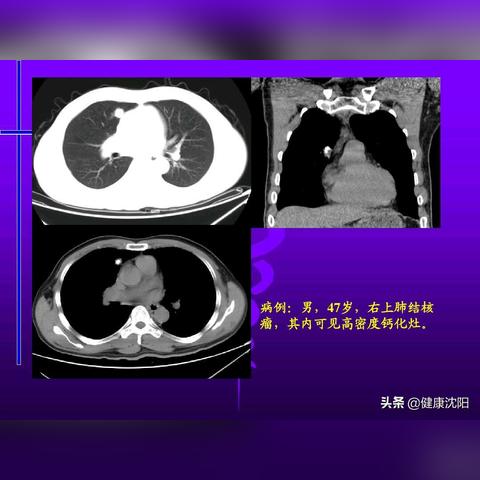

目前,基因检测和影像学检查是诊断结节性硬化症的主要手段,随着技术的发展,非侵入性的影像学检查如MRI和PET在诊断中的应用越来越广泛,生物标志物的研究也在不断深入,有助于早期诊断和病情监测。